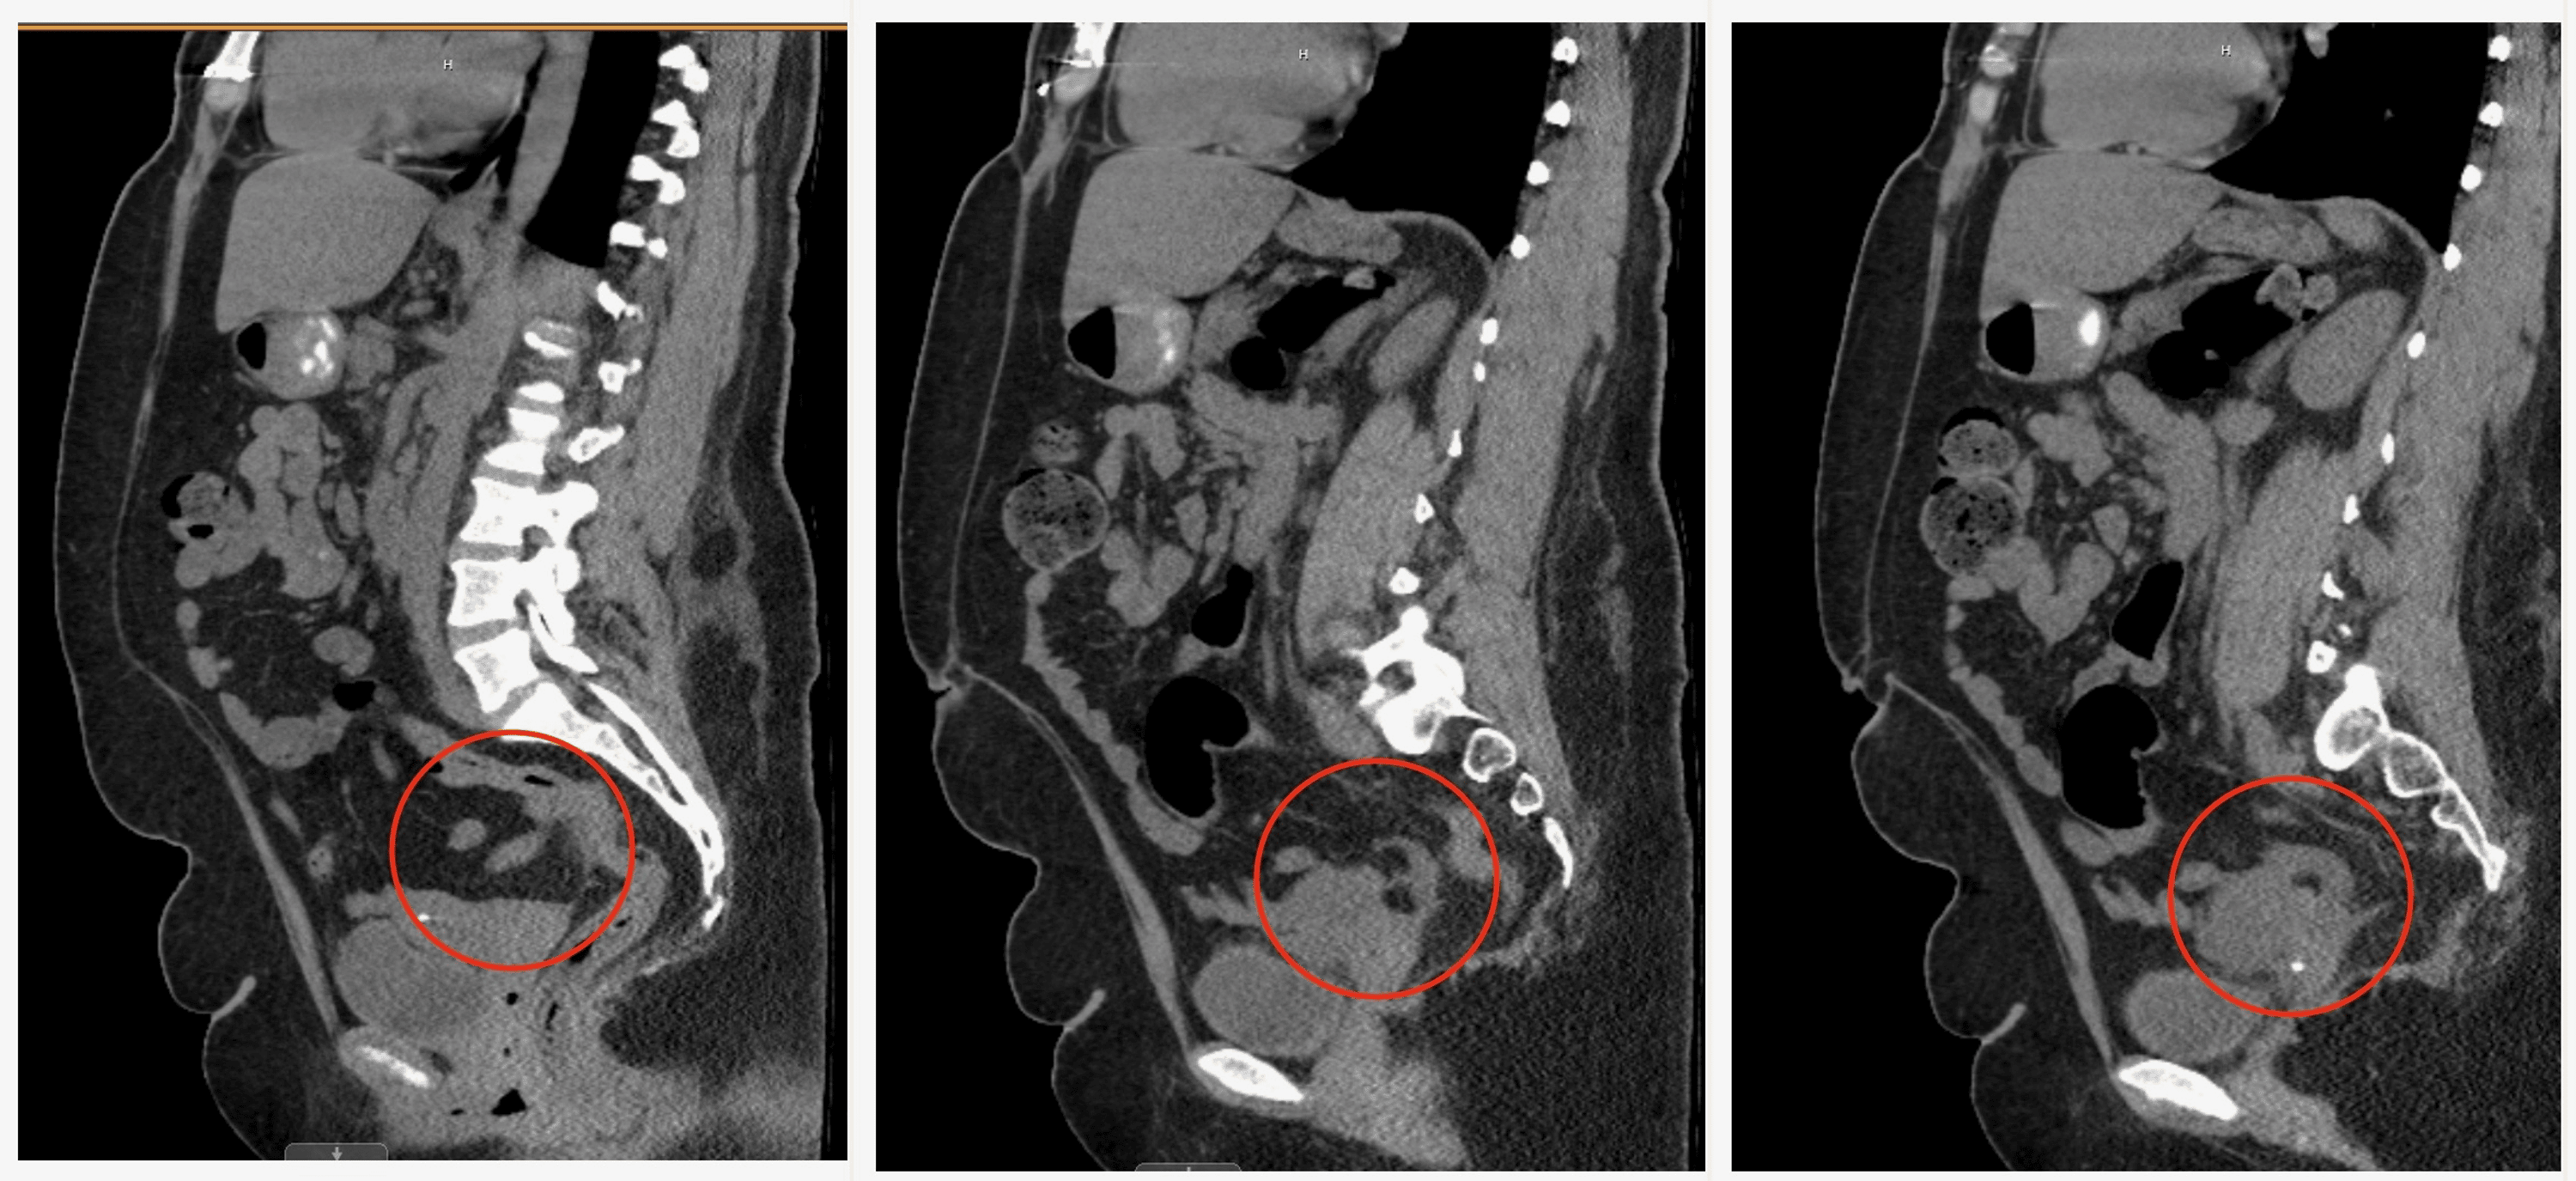

Case Report Of Perforated Appendicitis . We present this unusual case of abdominal pain secondary to extraperitoneal compartmentalized abscess following. Recurrent appendicitis can be missed or delayed secondary to atypical. Despite characteristic clinical signs, diagnosis can be. According to laboratory and radiographic data, the patient was diagnosed. Acute appendicitis is a common cause of acute abdominal pain requiring urgent surgery.

We present this unusual case of abdominal pain secondary to extraperitoneal compartmentalized abscess following. Acute appendicitis is a common cause of acute abdominal pain requiring urgent surgery. Despite characteristic clinical signs, diagnosis can be. Recurrent appendicitis can be missed or delayed secondary to atypical. According to laboratory and radiographic data, the patient was diagnosed.